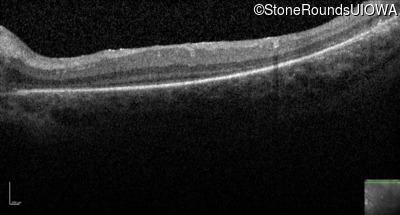

Optical Coherence Tomography - Right -

No Light Perception

Exemplar

Expanded OCT Stack

×